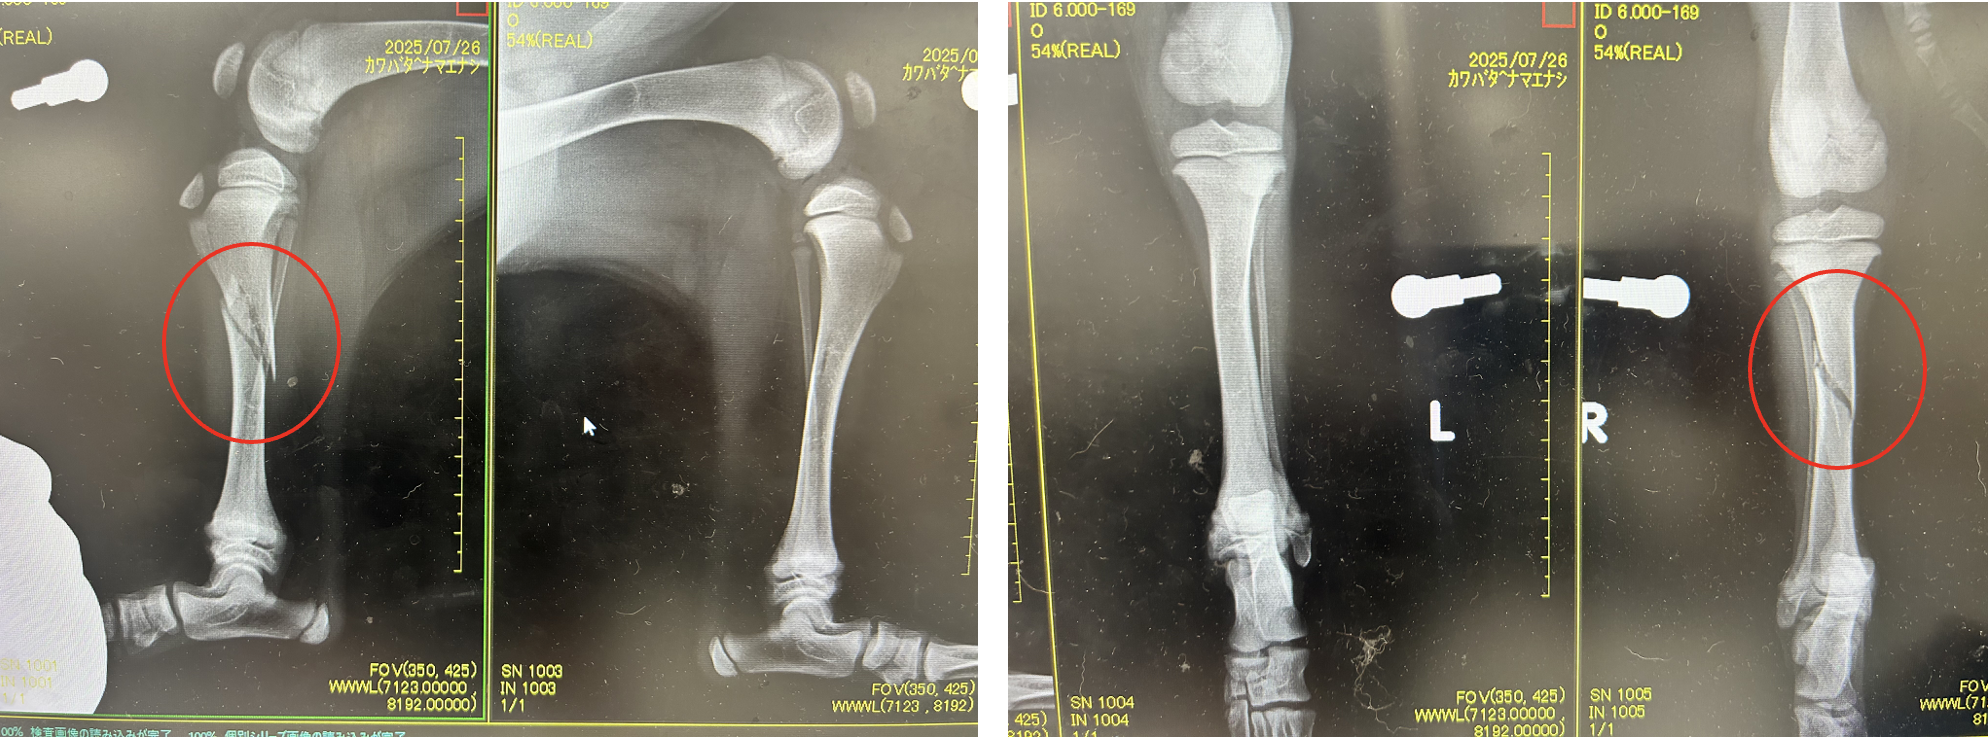

レントゲン、CTより右脛骨の斜骨折または螺旋骨折が認められた

中和プレート固定、ラグスクリュー

before

after